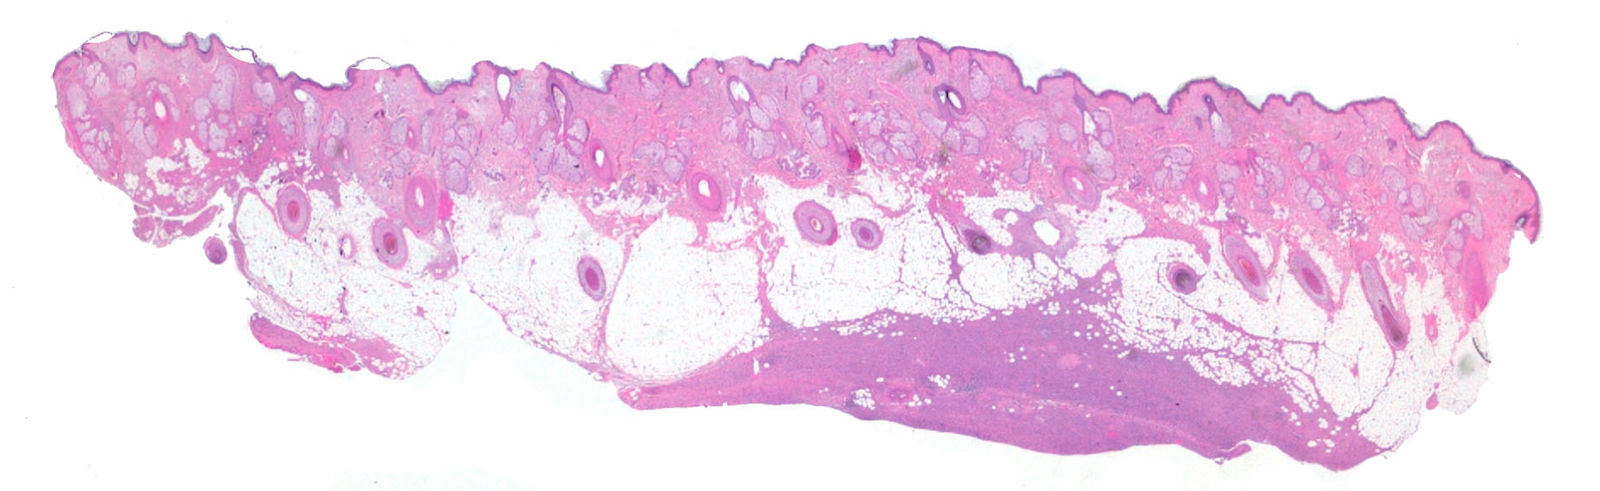

Clinically, head DFSP often presented as ill-defined indurated tumoral plaques (13/32, 40.6%) or as subcutaneous nodules (6/32, 18.8%) without surface skin changes or alopecia, thereby mimicking lipomas or cysts (Fig. 1). In contrast, body DFSP more frequently showed the classic appearance of a plaque with protuberant nodules (98/203, 48.3%; P<.001). No significant differences in age, sex, or tumor size were observed between head and body DFSP (Table 1). Mean time to diagnosis was 132.7 months and was shorter for head DFSP than for body DFSP (104.1 vs 137.3 months, respectively; P=.047).

Histologically, all lesions showed a moderate proliferation of spindle cells with mild pleomorphism and CD34 positivity. No differences in CD34 staining pattern or intensity were observed according to tumor location. Most tumors showed storiform and cartwheel patterns (204/235, 86.8%). The compressive pattern of subcutaneous tissue infiltration was more common in head DFSP than in body DFSP (12/32, 37.5% vs 26/203, 12.8%; P=.005). No association was found between histologic subtypes previously described in the literature and tumor location. SC-DFSP was significantly more common on the head than elsewhere on the body (23/32, 71.9% vs 15/203, 7.4%; P<.001) (Figs. 2 and 3). Among head DFSP, time to diagnosis was shorter for SC-DFSP than for D-DFSP (68.3 vs 195.4 months; P=.005) (Table 2). Head DFSP also showed a greater tendency to invade deep structures, with focal infiltration of muscle or periosteum more frequently than body DFSP (26/32, 81.3% vs 38/203, 18.7%; P<.001) (Fig. 4).